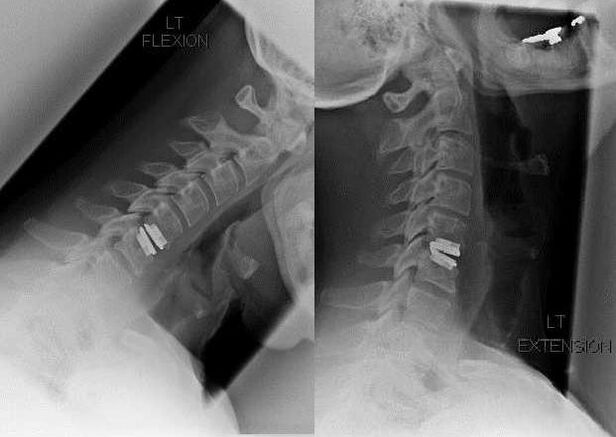

Chirurgischer Eingriff

Zu den Indikationen für einen chirurgischen Eingriff zählen die Unwirksamkeit einer konservativen Behandlung sowie Komplikationen der zervikalen Osteochondrose, beispielsweise diskogene Myelopathie, Wirbelarteriensyndrom und radikuläres Syndrom. Um das Rückenmark, die Blutgefäße und die Wirbelsäulenwurzeln zu entlasten, werden folgende Operationen durchgeführt:

Bei der Operation können Knochenfragmente und Bänder herausgeschnitten und Bandscheiben ganz oder teilweise entfernt werden. Bei kleinen Hernienvorsprüngen wird häufig eine Laserverdampfung des Bandscheibenkerns durchgeführt.

Nach der Entfernung von Wirbelstrukturen ist häufig eine Stabilisierung der Bewegungssegmente der Wirbelsäule durch eine Wirbelsäulenversteifung oder die Installation von Knochen- und Hautautotransplantaten erforderlich.